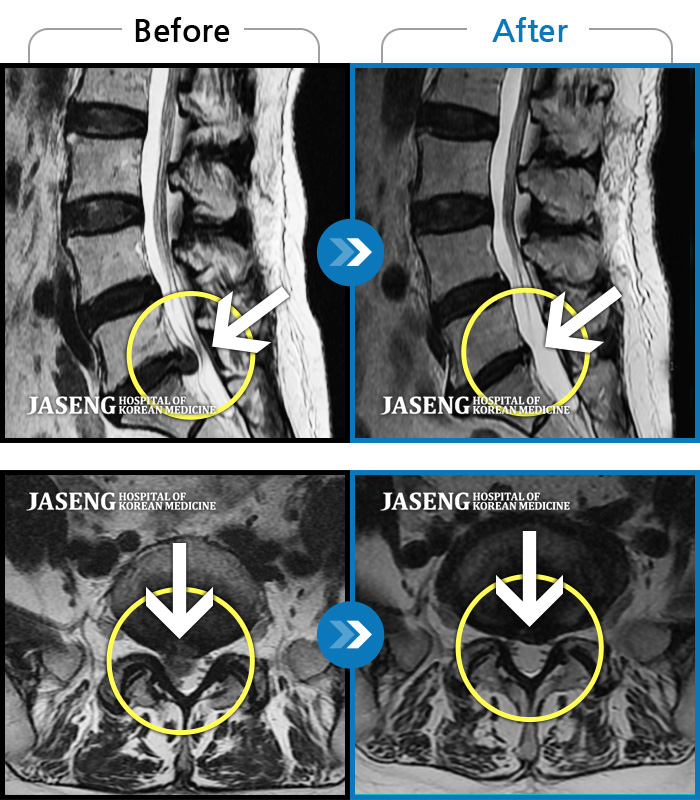

허리디스크

목동 · 고웅 원장

심한 왼쪽 엉치 통증. 종아리, 발바닥 저림

촬영시기

2020.10.14 ~ 2024.10.07

2024.12.24